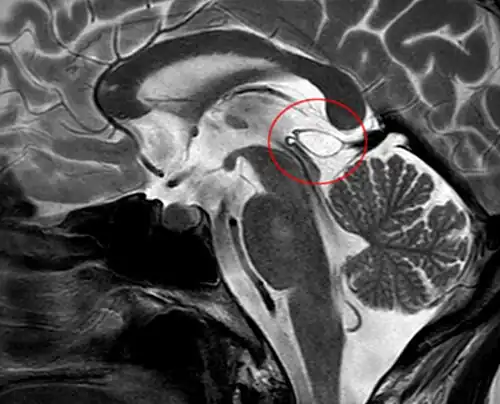

The National Organization for Rare Disorders states that pineal cysts larger than 5.0 mm are "rare findings" and are possibly symptomatic. If narrowing of the cerebral aqueduct occurs, many neurological symptoms may exist, including headaches, vertigo, nausea, muscle fasciculations, eye sensitivity, and ataxia. Continued monitoring of the cyst might be recommended to monitor its growth, and surgery may be necessary.[2]

Pineal gland cysts typically require treatment only if they are symptomatic. They can be removed either endoscopically [3] or through a conventional open approach, such as a supracerebellar infratentorial approach.[4]